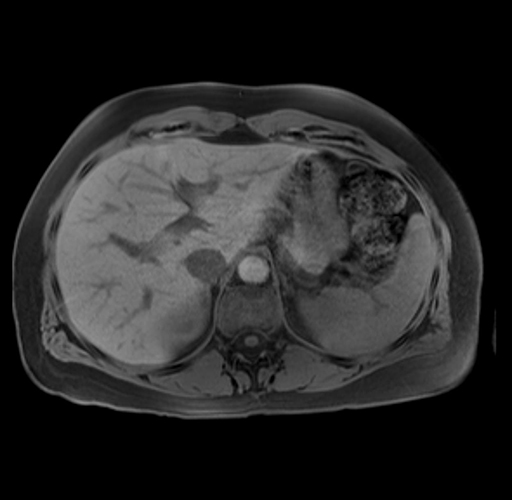

Imaging Analysis

Look through the patient's CT scan to identify any areas of concern for the necessary procedure.

Based on your CT findings, which issue(s) are present and would give reason for "planned slowing down moment(s)" in this case?